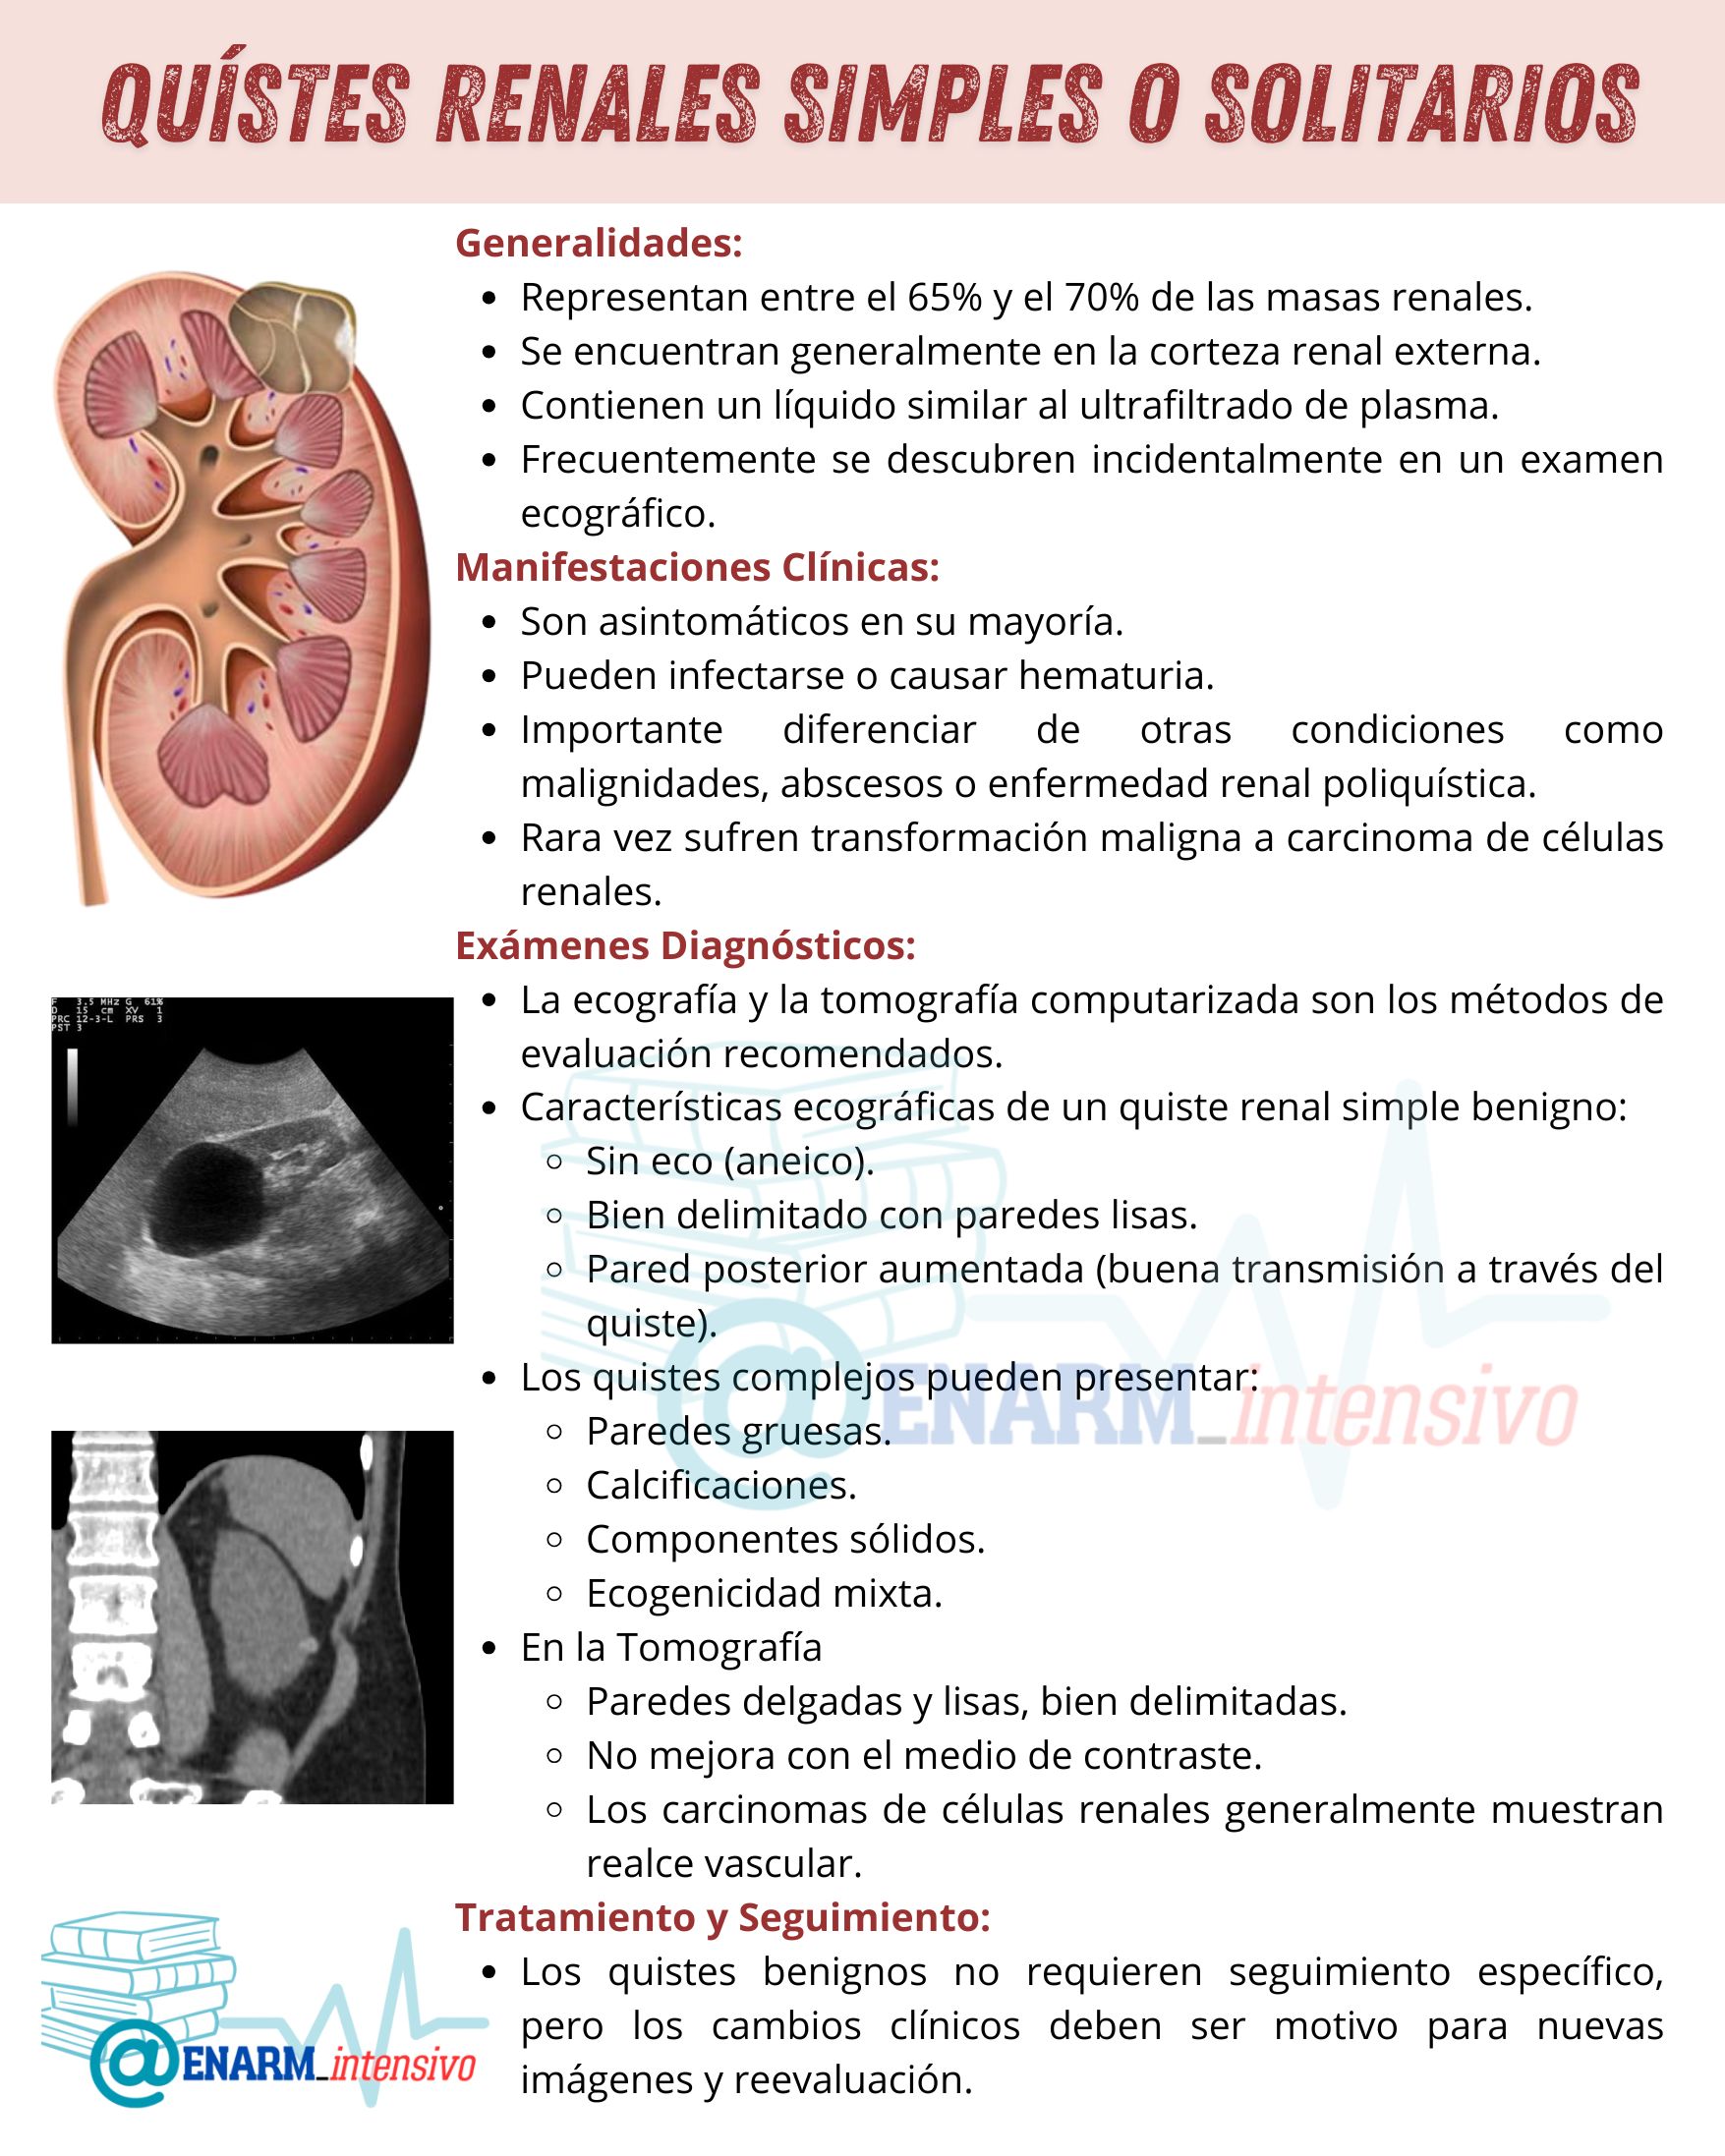

Ecografía: Este es el método más frecuente y accesible para la evaluación inicial de los quistes renales. En los quistes simples, se buscan tres características ecográficas esenciales que indican su benignidad:

Ausencia de eco: Los quistes simples son anecoicos, lo que significa que no generan señales de eco al ser atravesados por las ondas ultrasónicas. Esto se debe a su contenido líquido, que no refleja las ondas de manera significativa. Esta característica es un indicio clave de que el quiste es simple y no presenta componentes sólidos que pudieran sugerir malignidad.

Paredes bien delimitadas y lisas: Los quistes simples presentan bordes nítidos y suaves, sin irregularidades o engrosamientos. Las paredes lisas son indicativas de una estructura estable, sin signos de proliferación celular anómala, como ocurre en los quistes complejos o en tumores malignos.

Pared posterior aumentada: Este fenómeno, conocido como «refuerzo posterior», se produce debido a la buena transmisión de las ondas ultrasónicas a través del líquido contenido en el quiste. Esto significa que las ondas pasan a través del quiste sin obstáculos, lo que aumenta la claridad de la imagen en la parte posterior del quiste, un signo típico de un quiste simple.

Por otro lado, los quistes complejos presentan características diferentes. Estos pueden tener paredes gruesas, calcificaciones visibles, componentes sólidos dentro del quiste, y ecogenicidad mixta, lo que sugiere una naturaleza más intrincada y potencialmente patológica. Estas características requieren una evaluación más detallada para descartar malignidades u otras condiciones subyacentes.

Tomografía Computarizada (TC): En la tomografía computarizada, los quistes simples se identifican por su contenido homogéneo y paredes delgadas y lisas. Además, es importante que el quiste no muestre ningún tipo de realce con el medio de contraste, es decir, no debe mostrar una mayor intensidad en la imagen después de la administración del contraste intravenoso. La falta de realce con el contraste es característica de los quistes simples, ya que no presentan vascularización interna ni estructuras sólidas que puedan captar el contraste.

En contraste, el carcinoma de células renales, un tipo de cáncer renal, generalmente muestra un realce vascular. Esto significa que las áreas tumorales se enriquecen con el medio de contraste debido a su mayor irrigación sanguínea. Aunque algunos casos de carcinoma renal pueden ser avasculares (es decir, no mostrar realce), esta es una excepción y se debe investigar más a fondo. En estos casos, la TC es particularmente útil para diferenciar entre un quiste benigno y un posible tumor maligno.